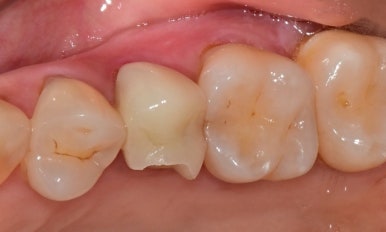

🧑⚕️ 남아 있는 치아는 건강할까?

파절된 보철을 제거한 뒤,

치아 상태를 정밀하게 체크했습니다.

✅ 다행히 치아 뿌리와 구조 모두 건강했고,

✅ 신경치료나 추가 보강 없이 바로 재보철이 가능했어요.